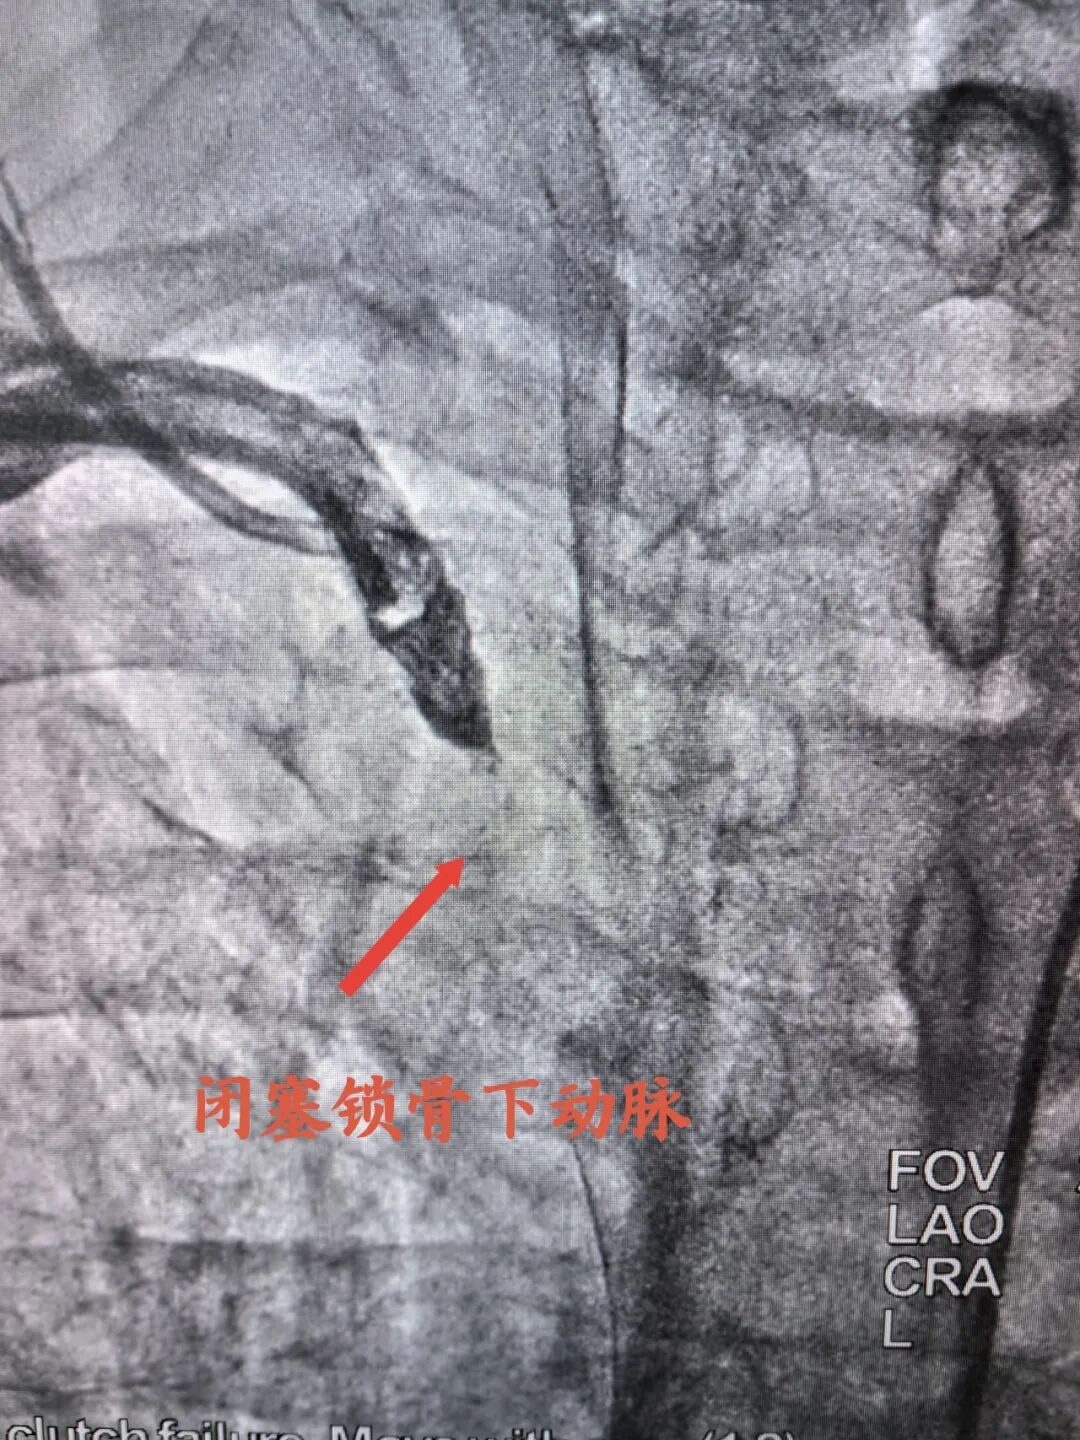

入院完善各项检查后考虑为冠心病合并右锁骨下动脉狭窄可能,经宋坤青主任团队研究后,决定为该患者施行冠脉造影+锁骨下动脉造影。经过严谨的术前讨论及充分的术前准备后,在2024年06月07日上午,宋坤青主任、赵博韬副主任及杨亚楠、冉德聪主治医师为该患者进行了造影手术,结果提示右冠状动脉近近段90%狭窄,前降支近中段90%狭窄,右侧锁骨下动脉闭塞。

闭塞锁骨下动脉